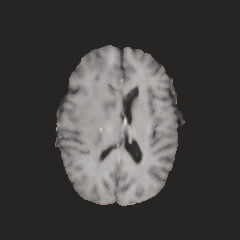

Multi-modal medical image completion has been extensively applied to alleviate the missing modality issue in a wealth of multi-modal diagnostic tasks. However, for most existing synthesis methods, their inferences of missing modalities can collapse into a deterministic mapping from the available ones, ignoring the uncertainties inherent in the cross-modal relationships. Here, we propose the Unified Multi-Modal Conditional Score-based Generative Model (UMM-CSGM) to take advantage of Score-based Generative Model (SGM) in modeling and stochastically sampling a target probability distribution, and further extend SGM to cross-modal conditional synthesis for various missing-modality configurations in a unified framework. Specifically, UMM-CSGM employs a novel multi-in multi-out Conditional Score Network (mm-CSN) to learn a comprehensive set of cross-modal conditional distributions via conditional diffusion and reverse generation in the complete modality space. In this way, the generation process can be accurately conditioned by all available information, and can fit all possible configurations of missing modalities in a single network. Experiments on BraTS19 dataset show that the UMM-CSGM can more reliably synthesize the heterogeneous enhancement and irregular area in tumor-induced lesions for any missing modalities.